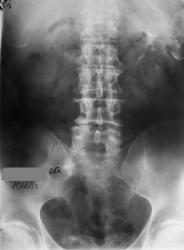

А Вы сделайте последний снимок через 12-24 часа от момента начала исследования...да с небольшим поворотом (левый бок чуть приподнять), вот тогда и посмотрим, то ли это тот "ежик" на уровне нижнего края S1 или та тень, что в малом тазу....то что камень в мочеточнике сомнений нет...но на что идти урологу...вот в чем вопрос.

Мне кажется, неоднородный камень или группа камней находится в устье правого мочеточника. Осталось неясным почему "оно" померкло на последнем снимке. Но Людмила Григорьевна умеет создать проблему на ровном месте, сама того не желая)). А в крестце вижу только очаг остеосклероза.

Виктор Григорьевич, проблема в том, что не факт, что через 12-24 часа поймаем контрастирование дистальной трети мочеточника. А КТ в нашем же отделении. Так что не стала выдумывать велосипед. Пациент получил диск, поедет в Тверь дробить руду

Петрович, Вы правы, но уже обжегшись, дую на кости - а вдруг там каменюка, а я за костные дела принимаю...